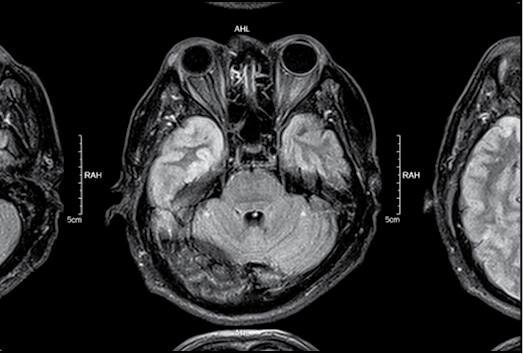

Иллюстрация к книге — Безумие ли? Как психиатры выставляют диагноз? [i_036.jpg]

Иллюстрация к книге — Безумие ли? Как психиатры выставляют диагноз? [i_037.jpg]

Иллюстрация к книге — Безумие ли? Как психиатры выставляют диагноз? [i_038.jpg]

Глядя на природу человека, часто отделяют биологическое (телесное) от психического. Но психика является продуктом деятельности головного мозга. Равно как и все процессы, в том числе болезненные, которые происходят в организме, отражаются на деятельности психики. И существует целый пласт психических расстройств, которые связаны с системными (то есть поражающими все части организма) заболеваниями. Моя врачебная практика началась с отделения сочетанной психической и соматической (телесной) патологии, и именно там связь между телом и духом ощущалась наиболее остро.